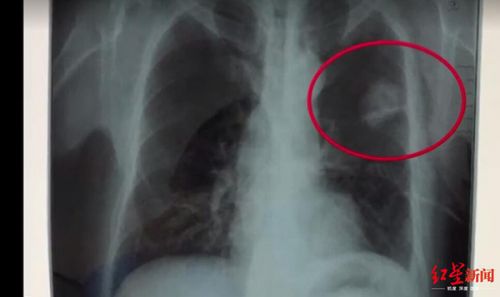

體檢胸片顯示的陰影

2018年5月7日,法院公開(kāi)開(kāi)庭審理了此案。四川勞研科技有限公司代理人在庭審中辯稱(chēng),陳志鵬體檢當(dāng)天,初審醫(yī)生在查看其胸片的時(shí)候,發(fā)現(xiàn)陳志鵬左上肺有陰影,將該情況記錄在案,并且在體檢當(dāng)天電話告知陳志鵬本人,詢(xún)問(wèn)其是否出現(xiàn)癥狀,并且建議其復(fù)查。但陳志鵬說(shuō),他沒(méi)有聽(tīng)到醫(yī)生要求摘掉自己所佩戴的玉佩,肺部的陰影應(yīng)該是玉佩所留,并且表示自己身體沒(méi)有出現(xiàn)任何不適癥狀。

在最終出具體檢報(bào)告前,體檢醫(yī)生再次致電陳志鵬,要求其進(jìn)行復(fù)查,但是他依然提出不用復(fù)查。在法庭上,檢查陳志鵬胸片的醫(yī)師出庭,法官對(duì)她進(jìn)行了詢(xún)問(wèn),該女醫(yī)師稱(chēng),“就是他(陳志鵬)一直說(shuō)戴了一個(gè)玉佩,正常說(shuō)來(lái)玉佩在胸片上,會(huì)顯示有陰影的,不可能就消失了,然后再問(wèn)他癥狀,他說(shuō)什么癥狀都沒(méi)得,也不咳嗽,也不胸悶,他說(shuō)正常的很,然后我們結(jié)合這些癥狀和胸片的情況,就出具了未見(jiàn)明顯異常的報(bào)告。”

法院一審認(rèn)為,患者的知情權(quán),是指醫(yī)療機(jī)構(gòu)及其醫(yī)務(wù)人員應(yīng)當(dāng)向患者如實(shí)告知病情、醫(yī)療措施、醫(yī)療風(fēng)險(xiǎn)等。本案中,被告在對(duì)陳志鵬進(jìn)行職業(yè)健康體檢時(shí),被告的醫(yī)師在發(fā)現(xiàn)陳志鵬肺部有陰影、存在問(wèn)題的情況下,在與陳志鵬聯(lián)系后,隨意認(rèn)為是陳志鵬自述的所謂的玉佩所形成的陰影,作為多年從事醫(yī)學(xué)行業(yè)的醫(yī)師,未遵守或履行一個(gè)醫(yī)師的職業(yè)道德和職責(zé),不負(fù)責(zé)任地在報(bào)告單上出具了“心肺膈未見(jiàn)明顯異常”的結(jié)論。